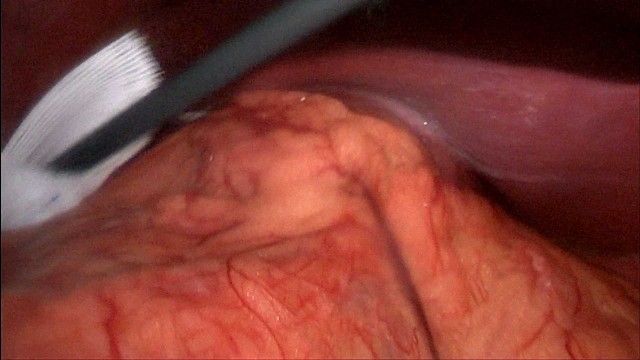

烧伤整形邹普功烧伤科医师

活动背景和目的:我从去年九月份陆续在丁香园写了几十帖有关腋臭微创手术的帖子,受到很多同行老师的关注及跟帖,其中有很多同行老师也在尝试用我的这种方法治疗狐臭,并且收到很好的效果。随着站内外科同行对狐臭微创手术的关注度日渐增高,近期受丁香园邀请,特举办一次关于狐臭微创手术的跟学练活动。这也是本人根据临床工作中的一些手术案例总结的经验,分享给大家一起交流学习。让我们一起做好除臭这件事!各位站友可点击下面狐臭专场链接交流学习(包含本人视频操作教学详解、常见问题讨论和各位站友同行的手术佳作):https://3g.dxy.cn/newh5/view/nodeActivityTopic/270第一期我给大